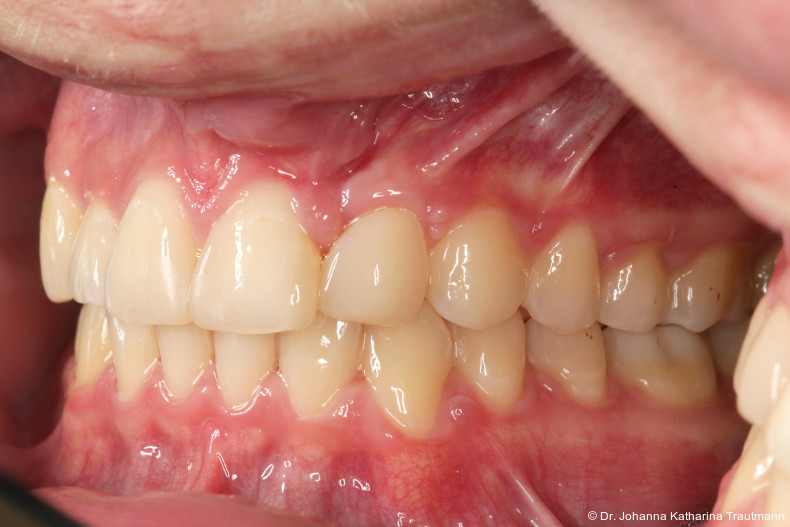

Längere Retentionszeiten ohne odontoplastischen Umbau können das Risiko eines Rezidivs des Zahnes 22 erhöhen. Dennoch ist häufig eine Abheilphase nach der Multibrackettherapie erforderlich, da sich gingivale Entzündungen oft erst nach ein bis drei Monaten vollständig zurückbilden.19–21 Um diesen Zeitraum zu überbrücken wurde an 22 die Kunststoffbasis der DVP (Doppel vorschubplatte) zur Retention sowohl mesial als auch distal extendiert. Schließlich wurden die Zähne 11, 21 und 22 kompositrestaurativ angeglichen, wodurch ein sehr gutes ästhetisches Ergebnis erzielt wer den konnte. Aufbauten mit Komposit bieten eine gute Möglichkeit, bei maximaler Schonung der Zahnhartsubstanz hypoplastische Zähne langfristig zu versorgen, und zeigten in ZehnJahresFollowups hohe Überlebensraten. Entscheidend ist hierbei eine ausgeglichene okklusale Lastverteilung, die mit hilfe einer physiologischen Frontzahnabstützung und gesicherten Okklusion durch die kieferorthopädische Vorbehandlung erreicht werden kann.22

Zur objektiven Quantifizierung des Behand lungsergebnisses wurde der Peer Assess ment Rating(PAR)Index erhoben.23 Im vorliegenden Fall konnte der PAR-Wert von 25 auf zwei reduziert werden, was einer Verbes serung von 92 Prozent entspricht und als hoch wertiges okklusales Ergebnis einzustufen ist.24 Zur Vorhersage der Langzeitstabilität bei Spalterkrankungen lässt sich dieser Fall in die Gruppe 1 des GOSLON Yardstick Index ein ordnen. Dieser sagt eine exzellente Langzeitstabilität vorher.25 Auch der Patient zeigte sich mit dem Ergebnis sehr zufrieden. Während der anderthalbjährigen Retentionsphase erfolgte zusätzlich eine ästhetische Nasenkorrektur zur Aufrichtung des linken Nasenflügels, wodurch neben der dentalen auch die extraorale Rehabilitation erfolgreich abgeschlossen werden konnte.